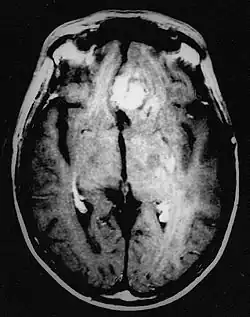

En las imágenes de TC y RM se muestra como una lesión heterogénea, de contorno irregular, que capta contraste en anillo y con un área central necrótica.

Diagnóstico por imagen y glioblastoma

La TC muestra una lesión de morfología irregular, predominantemente hipodensa y fuertemente dishomogénea, debido a la presencia de grandes áreas necróticas de más clara hipodensidad y de áreas sólidas hiperdensas. Estas últimas son la expresión de un rápido crecimiento y por lo tanto de una elevada malignidad. Son frecuentes las zonas hemorrágicas, que van desde pequeños focos a grandes áreas hemáticas que pueden cubrir toda la lesión. Es característica la morfología en "mariposa" si el tumor se asienta en ambos hemisferios a través del cuerpo calloso.

Tras la aplicación de contraste aparecen gruesos anillos alrededor de las áreas necróticas. En la RM, la parte sólida aparece hipointensa en T1 e hiperintensa en T2 con zonas de señal más elevada en las partes de mayor celularidad. Las áreas necróticas, hiperintensas en T2, pueden presentarse hipo-, iso- o hiperintensas en T1 en función del contenido proteico o de productos de la degradación de la hemoglobina. El realce tras el contraste suele ser intenso e irregular en la periferia del tumor e identifica sobre todo la componente celular "proliferativa" de la neoplasia. Son comunes las áreas puntiformes y serpiginosas de ausencia de señal de flujo, asociadas a la presencia de una neovascularización rica. Estos vasos de neoformación patológica carecen de barrera hematoencefálica, lo que explica tanto la abundante impregnación como el edema vasogénico perilesional (véase la sección anterior), debido al paso de líquido al medio extracelular.[72][73]